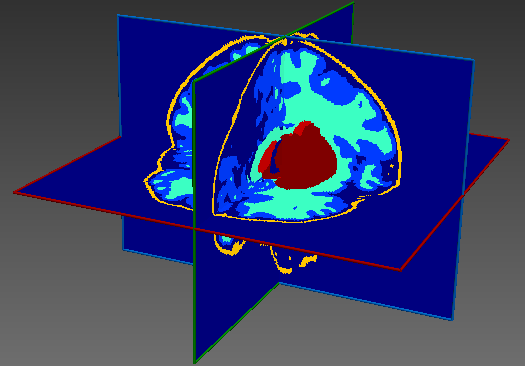

The dataset consisted of 70 3D T2-weighted brain MRI scans publicly available from the dHCP neonatal cohort. The segmentation maps had 10 classes, corresponding to: zero-pixel background, cerebrospinal fluid (CSF), cortical grey matter (cGM), white matter (WM), background bordering brain tissues, ventricles, cerebellum, deep grey matter (dGM), brainstem, and hippocampus. The scans covered an age range of 24.3-42.2 weeks. The data was available in NIfTI format; Figure 1 shows an example scan and corresponding tissue labels. We carried out a pre-processing step where each scan was independently normalised to zero-mean and unit-variance.